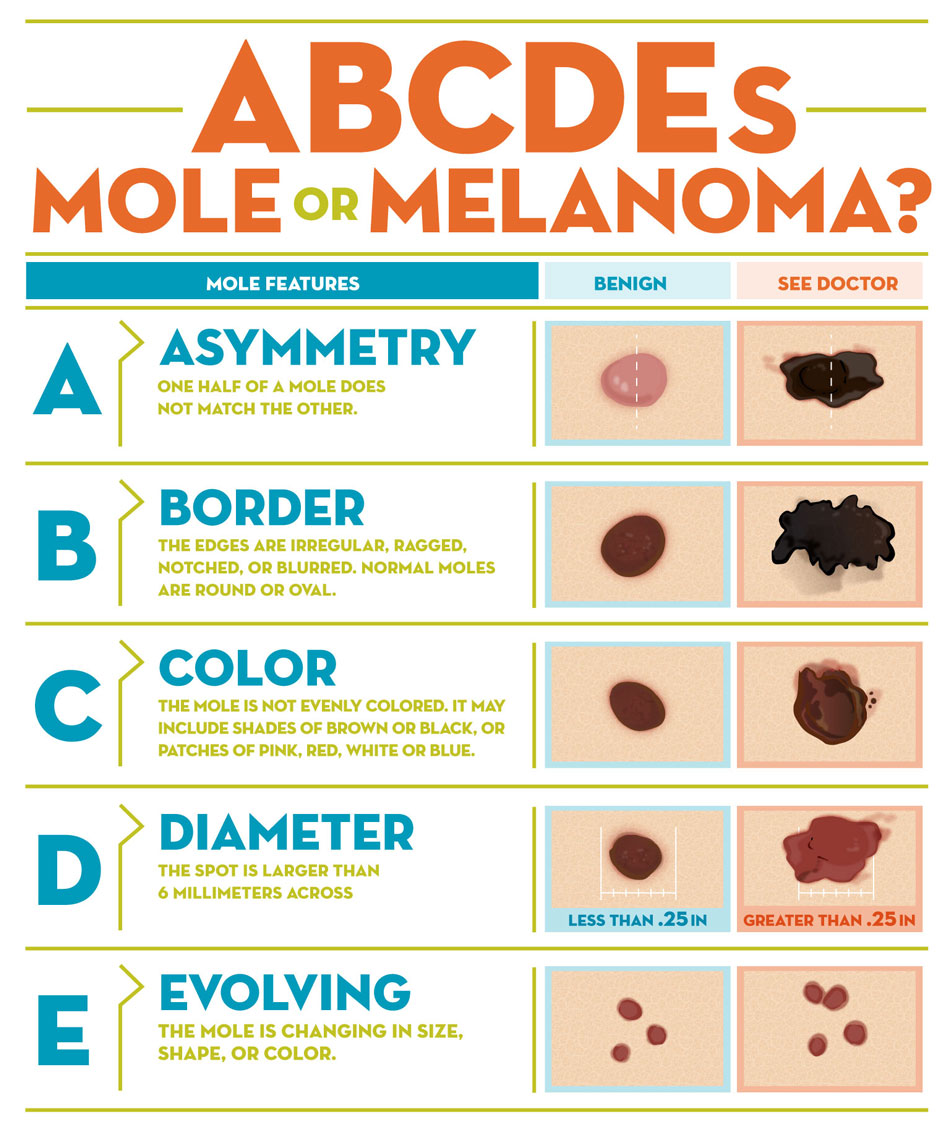

Melanoma (惡)

可以從 Melano cell, Naevus 轉過來,多變,甚至可以沒有 Pigmentation

ABCDE

- Asymmetry

- Border irregularity

- Color variegation

- Diameter >6mm

- Evolving